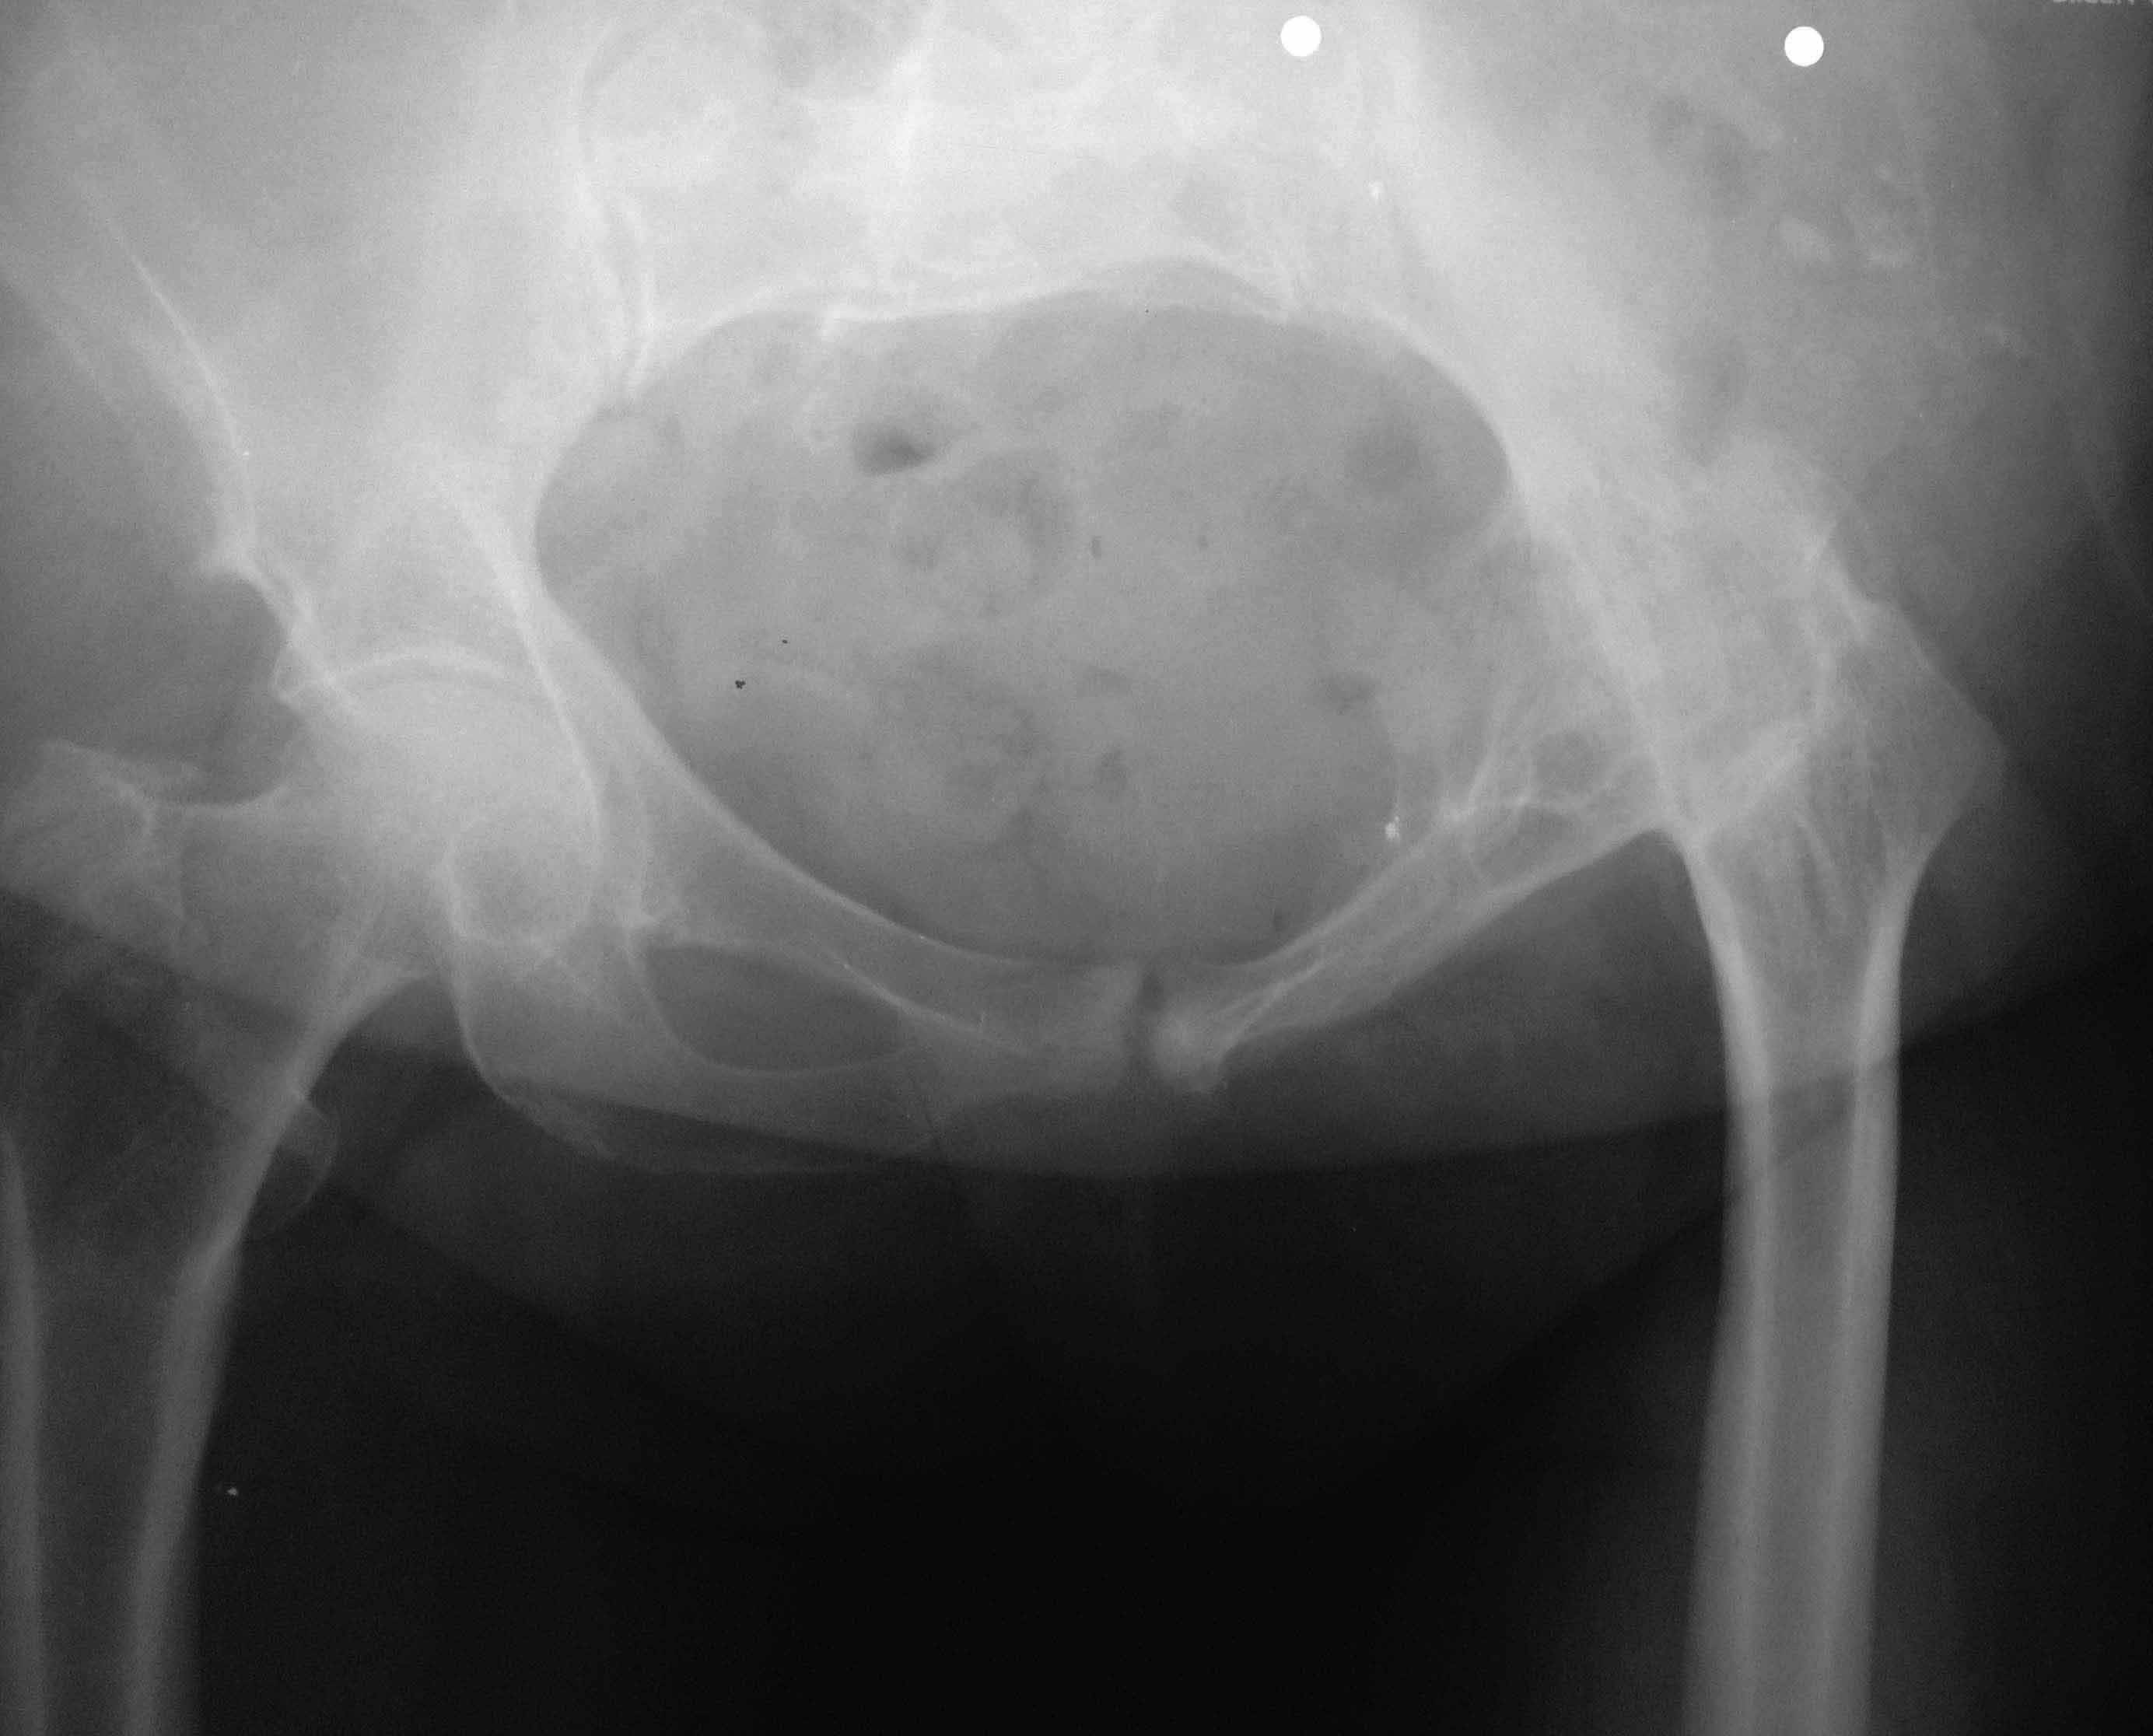

Рентгенологически костный анкилоз. Клинически сгибательно-приводящая контрактура. Ходит без средств опоры с выраженной хромотой. Больна с 10 летнего возраста. Сейчас пациентке 63. Жалуется на умеренные боли в области анкилозированого сустава, хотя складывается впечатление, что болевой синдром обусловлен позвоночником. Если у вас есть опыт операций при подобной деформации посоветуйте оперировать или нет.Выкладываю рентгеновские снимки. Могу выложить данные компьютерной томографии и видео походки.

Проблема здесь не в тазобедренном суставе которого нет. Проблема в позвоночнике, крестцово-подвздошном сочленении. Возраст 63 года наводит на мысль о декомпенсации всей опорно-двигательной системы, особенно в условиях порочного положения конечности. Операция эндопротезирования технически возможна, но при этом надо иметь ввиду, что давая свободу движений, а эта свобода к сожалению будет не столь велика, больная будет иметь стойкое ощущение нестабильности в суставе в виде "провала" при ходьбе, т.е. выраженный с-м Тренделенгбурга+ походка Тренделенбурга. Решая одну задачу - устранение порочного положения и давая движение в суставе, мы создаем проблему в виде выраженный хромоты, и постоянной необходимости в пользовании тростью. Я всегда стараюсь объяснить это пациентам, т.к. решение всегда за ними. Хотя технически операция тоже не простая и имеет много подводных камней.

На самом деле в этих операциях много технических нюансов: доступ должен обеспечить сохранность мышц (если они есть) и максимальную визуализацию шейки с целью выполнения корректно ее опила. Положение чашки: кроме того что надо попасть в анатомическое положение, необходимо задать горизонтальную инклинацию не более 40 град для профилактики вывиха, антеверсия 20-25 град, но ведь там скорее всего кифоз поясн. отдела позвоночника.... С ножкой проще, но важно сохранить укорочение минимум 1см. И все же главный вопрос делать-не делать. Боли в позвоночнике будут прогрессировать, и другого варианта как "развязать" сустав нет. Но учитывая сказанное мною ранее, выбор только за пациенткой. Как-то так